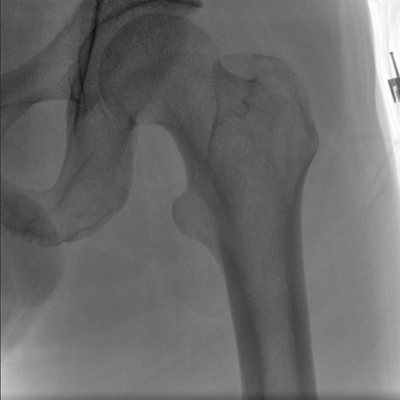

動態(tài)板C形臂 開啟清晰影像新篇章

大尺寸動態(tài)平板探測器,高DQE、低噪聲、圖像清晰。采用多分辨率圖像增強處理技術(shù),不同部位不同圖像處理算法,滿足客戶多樣化的需求。

采用智能變頻脈沖透視技術(shù),優(yōu)化圖像質(zhì)量的同時降低輻射劑量,呵護醫(yī)患健康